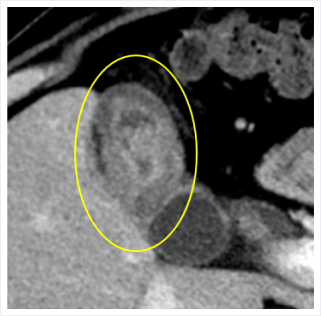

腹部エコーやCT、MRI検査を行いますが、画像所見はびまん性や局在性の壁肥厚など、様々な形態をとり、癌との鑑別が非常に難しいです。

隣接する肝臓や十二指腸にも炎症が波及することもあり、胆嚢癌で上昇することが多い腫瘍マーカー(CA19-9など)が上昇することもあります。

胆嚢壁の肥厚を認め、胆嚢癌との

鑑別が困難な場合があります